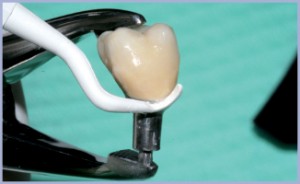

Dopo le prove estetiche e occlusali, abbiamo cementato la nostra corona sul moncone all’esterno del cavo orale, così da poter rimuovere perfettamente gli eccessi del cemento stesso (figg. 22-25); abbiamo quindi inconato il manufatto sulla fixture tramite doppia percussione (figg. 26-28).

- Fig. 22

- Fig. 23

- Fig. 24

- Fig. 25